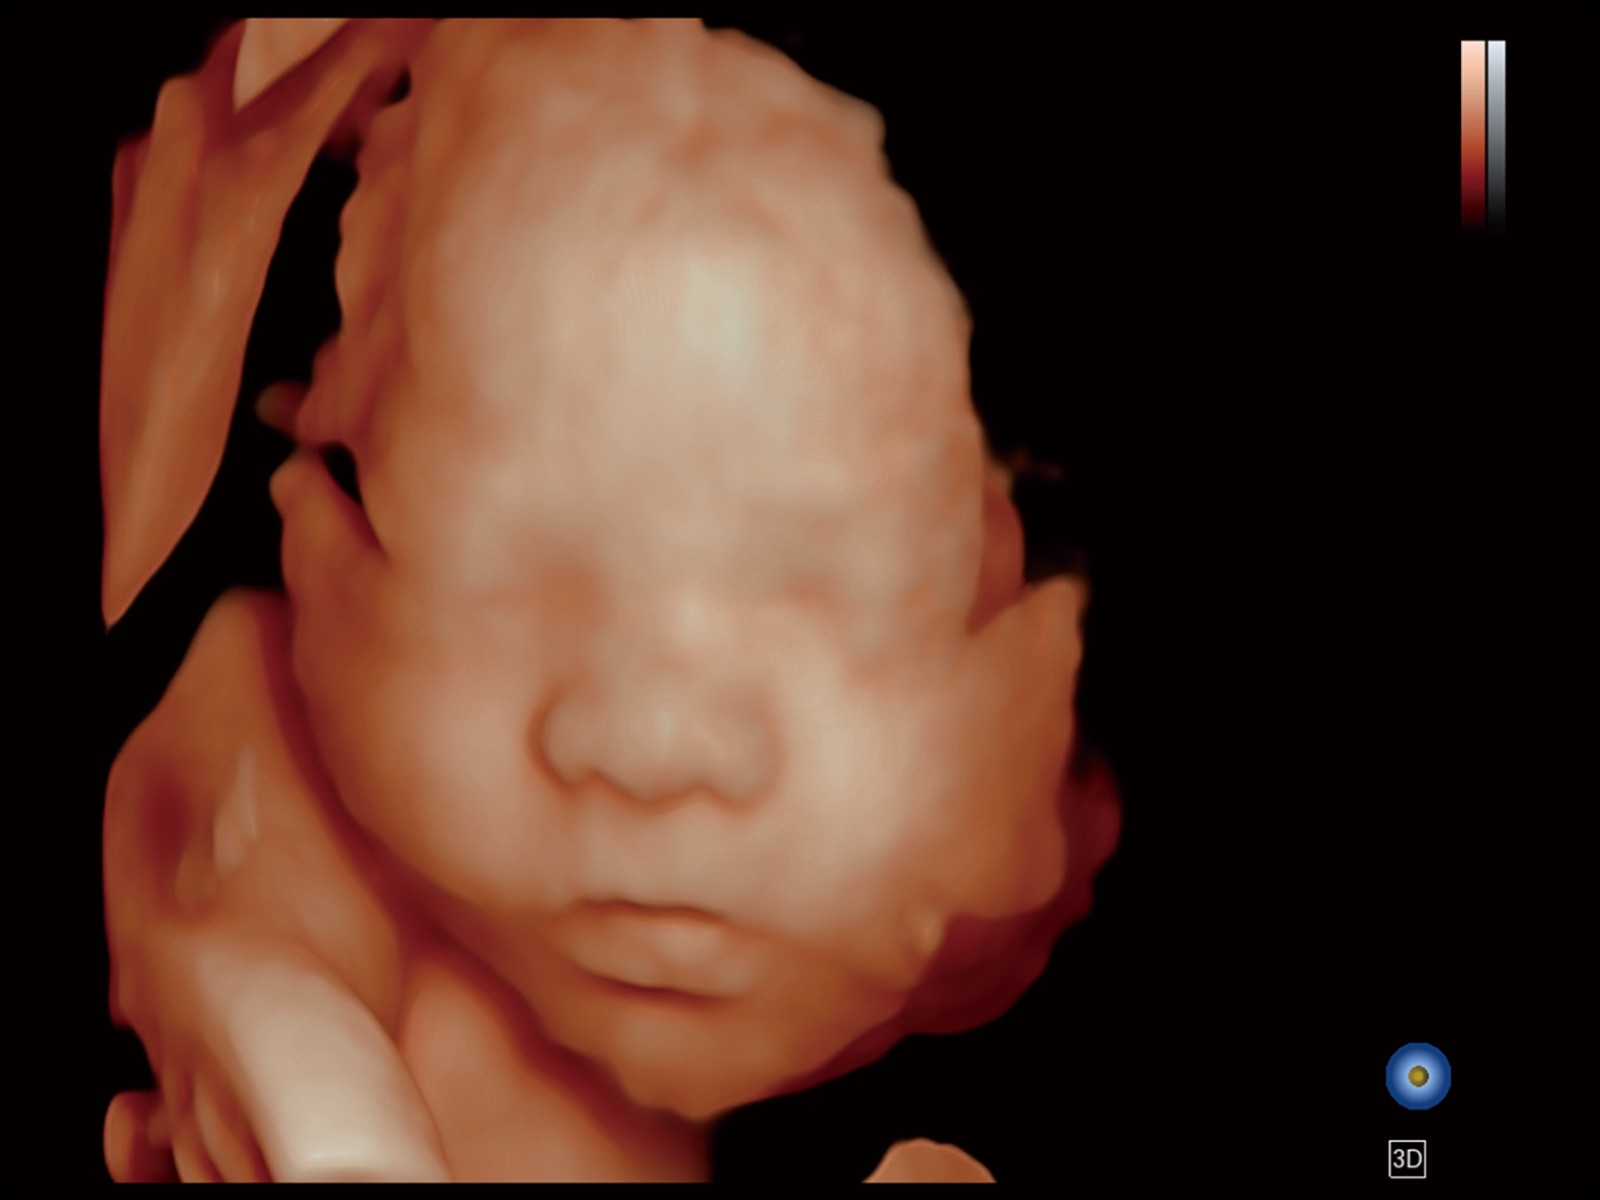

妇产应用